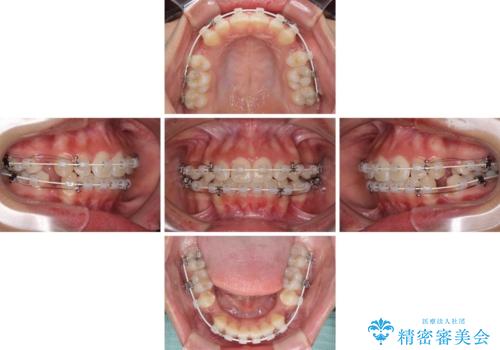

- 審美装置

- 1年7ヶ月

- 10-30回

前歯部の突出と開咬は、舌突出癖によるものでしたので、舌のトレーニングをしっかりと行っていただき、1年半程度と短期間で治療を終えることができました。